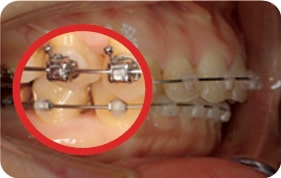

Case 1

2017. 07. 28

2017. 12. 05

2018. 03. 20

2018. 04. 28